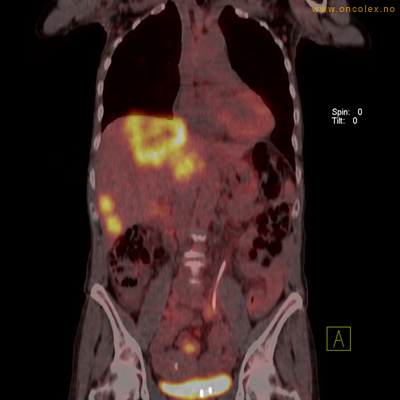

Vev som tar opp mer radioaktivt stoff, synes som hvite områder som lyser opp mer i forhold til annet vev som tar opp mindre sukker.

Adenokarsinom langt nede i spiserøret.

Høyt opptak av 18F-FDG i adenokarsinom i rektosigmoideumovergangen. Fysiologisk opptak i blæren.

Spredningssvulster til lever med sentral nekrose.